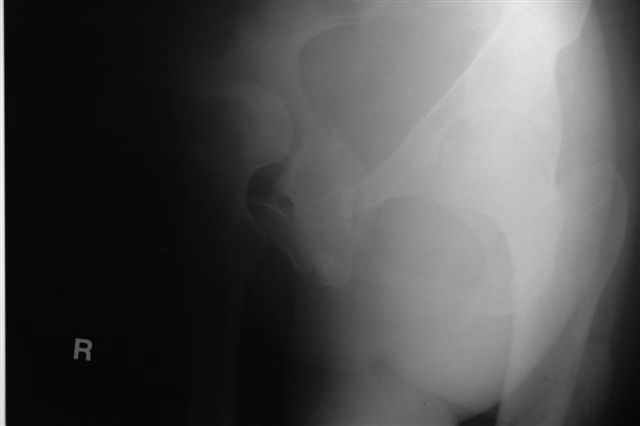

P.S. в приложении R пациентки с похожей проблемой доступа.. за исключением того, что перелом

двухколонный. Вертлугу лечили Y доступом.